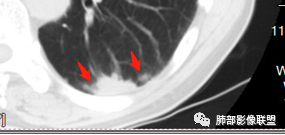

初学者:脐凹?

大部分病灶都是平直。一元就是肉芽肿性炎:隐球菌,类风湿结节。。二元就是这个脐凹,局部膨隆和坏死的家伙是二元肺癌。

南边:糊墙,长轴与胸膜平行;边缘收缩+膨隆;脐凹征

脐凹征,高度提示恶性

南边老师论述:    分叶凹陷的地方有血管,支气管进去,这个价值很大,后来引申到血管、支气管从凹陷的地方进去就叫脐凹征,就像番茄柄🍅,辣椒柄、苹果柄🍎一样的。后来就把这个做为脐凹征,95%以上的特异性。如下例:

后来发现胸膜牵拉,由远端凹陷的地方进去,他的价值也很大,诊断腺癌,几乎很少失误,后来把这个也纳入到脐凹征里。由凹陷处进入的胸膜牵拉征,由凹陷处进去的血管,都属于脐凹征。原理是由凹陷处进去的血管,因为肿瘤膨胀生长,生长过程中遇到血管,支气管区域受阻,边缘代偿性生长,膨胀的更厉害了,所以局部凹陷,前提是血管、支气管肯定在肺门侧,不会在远端有一条血管阻碍他的,可能性太小了。

脐凹征,支气管、血管引起的在肺门侧,因肿瘤生长在近端膨胀受阻的,病灶本身围绕支气管、血管周围包绕的不算,只有进去其中受阻的才算。